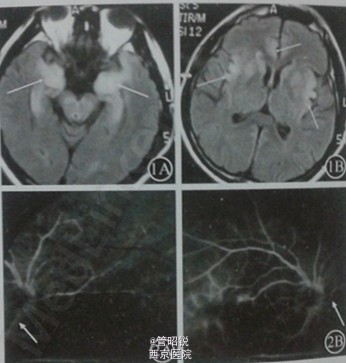

患者,男,因“发热11天,精神异常6天,意识障碍2天”入院。患者发病前1周有流涕、咳嗽症状。查体:双肺呼吸音粗,中度昏迷,查体不合作,双侧瞳孔对光反射迟钝,颈强直,双Kerning征阳性。6天后,意识转清;行走起步及转弯较缓慢,双上肢及头部出现静止性震颤。但患者入院6天后清晨述视觉障碍,无光感,查体见双侧瞳孔扩大,直接、间接对光反射消失。眼科会诊:上方和鼻侧及下方视网膜分支动脉闭塞,多处视网膜坏死灶。修正诊断:单纯疱疹病毒性脑炎,急性视网膜坏死综合征,帕金森综合症 3周后患者脑炎症状明显好转,而视觉障碍无好转。